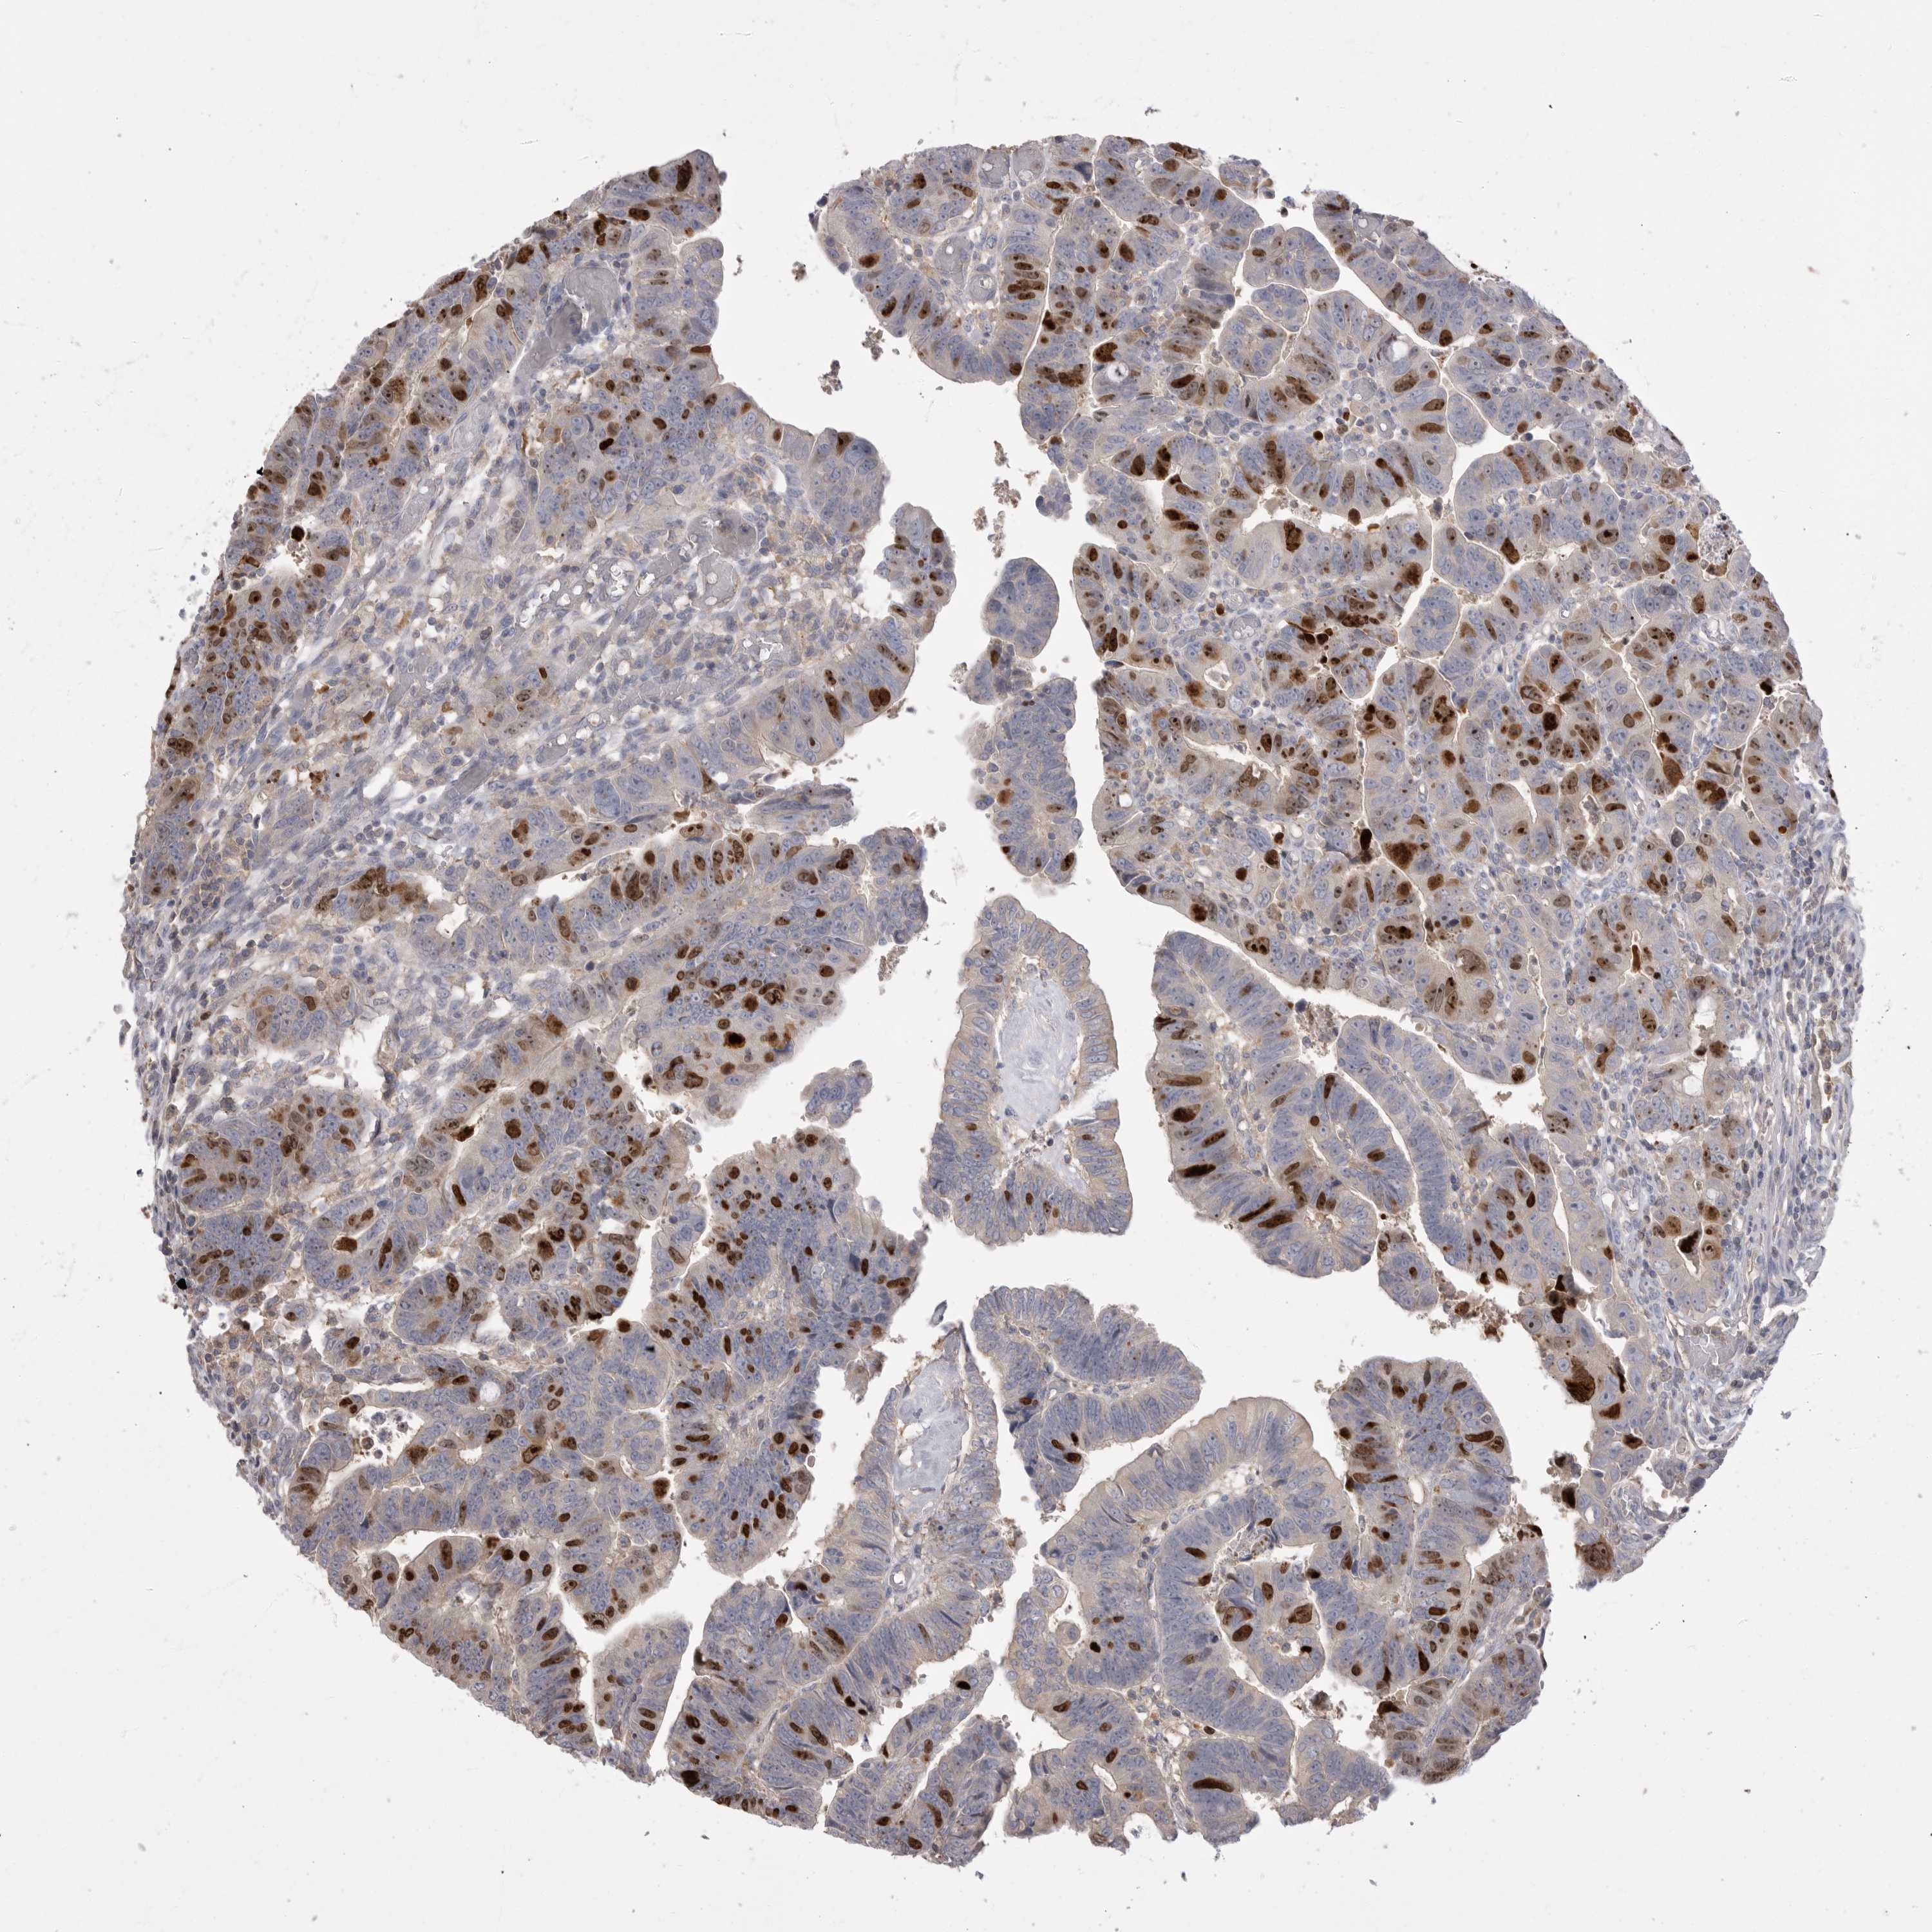

CANCER COLORECTAL CANCER Show tissue menu

Colorectal cancer

Human cancer

Colon adenocarcinoma

Rectum adenocarcinoma